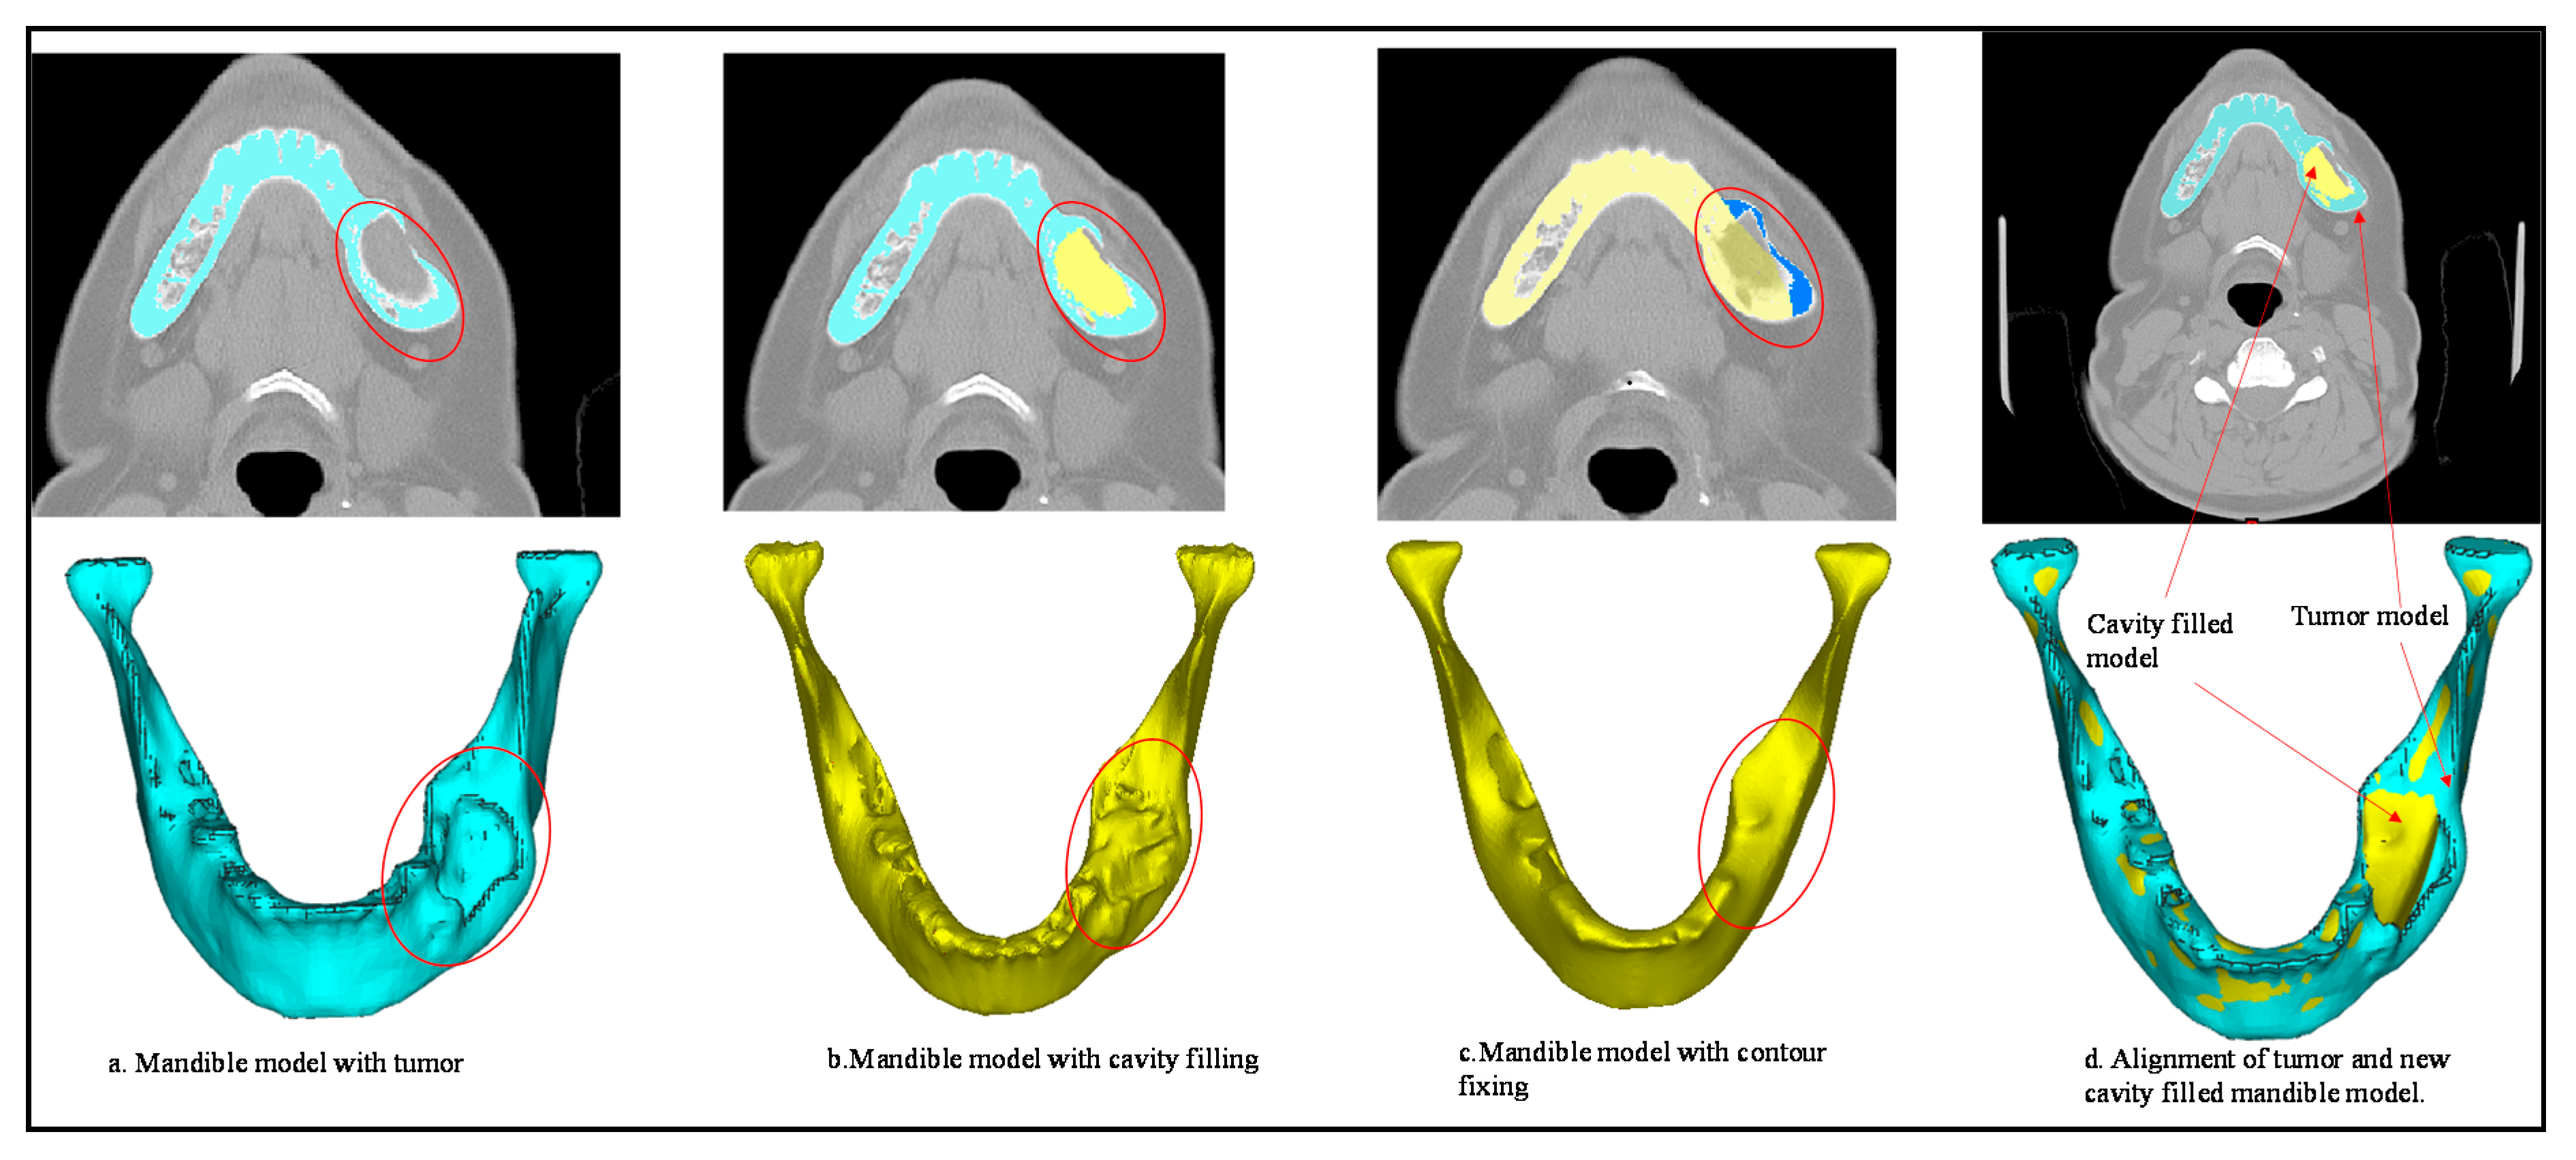

2.2. Image Acquisition and Processing

2.3. Custom Implant Design